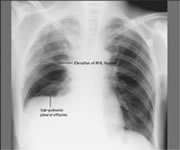

3、X线检查X线特点为均匀致密阴影,占据一侧胸部、一叶或肺段。阴影无结构,肺纹理消失及肺叶体积缩小。一侧或大片肺不张时可见肋间变窄、胸腔缩小。阴影位置随各肺叶肺不张的部位而异。下叶肺不张在正面胸片中成三角形阴影,位于脊柱与膈肌之间,在侧片中则靠近后胸壁。若系上叶肺不张,则正面、侧面影均呈楔形,其尖端向下并指向肺门。若系右侧中叶的肺不张,其正面阴影呈三角形,底部位于心影的右缘,尖端指向外侧;其侧影为一楔形,底部近前胸壁,位于膈肌之上,尖端向后及向上。在幼婴时期,除代偿性肺气肿之外,其他代偿现象如气管与心脏移位及膈肌上升,可暂不凧??,直至肺不张持续较久后才发生。但由于表面活性物质不足造成的微型肺不张,肺多呈毛玻璃状阴影,X线表现与小叶肺炎无异。

2.胸部X线片:显示肺不张,X线检查起主要诊断作用,尤以****为简捷。但局限于一个肺叶的肺不张,有时很难与肺炎区别,须参照肺叶解剖位置来考虑。必要时可作支气管镜检查以确定梗阻的部位及性质,同时也可作适当治疗。